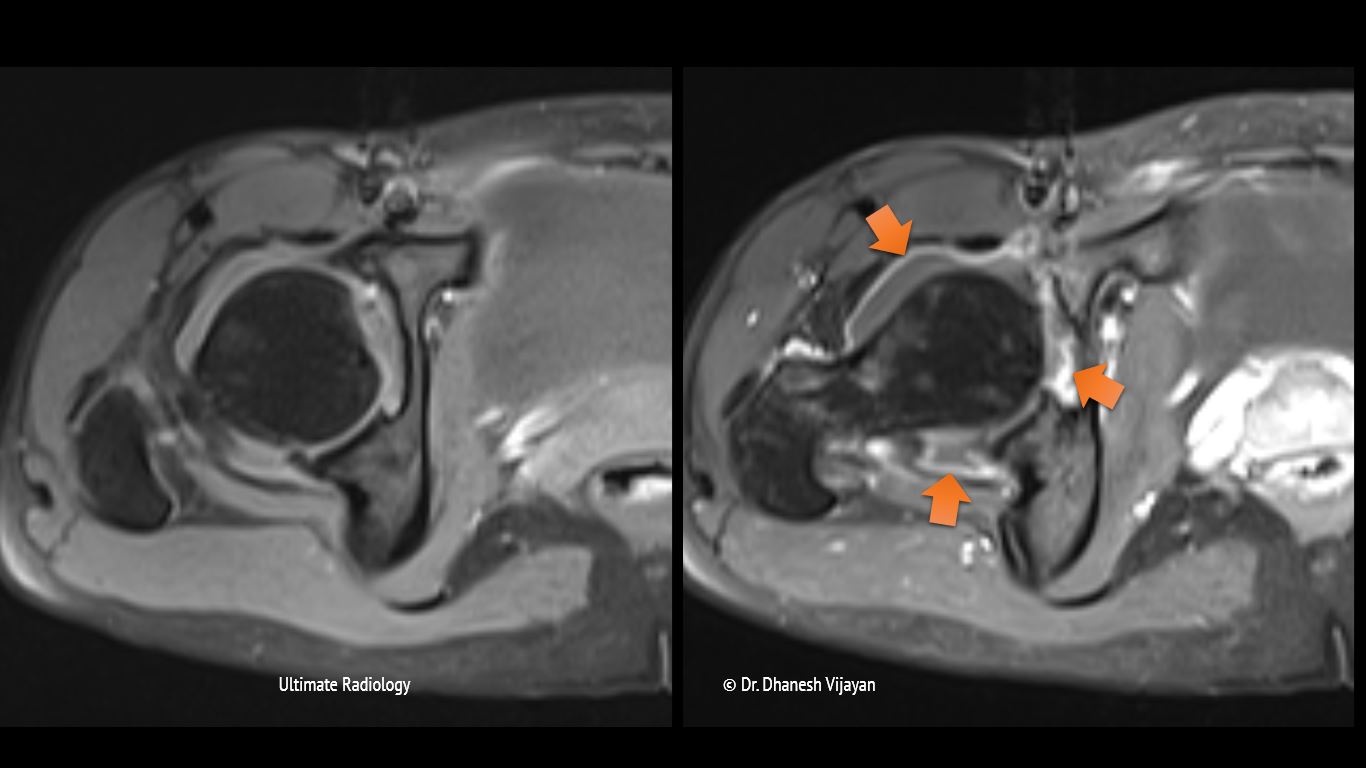

From ultimate-radiology.blogspot.com

Ultimate Radiology Septic arthritis of hip joint Septic Arthritis Icd 10 Left Hip septic arthritis is caused by joint infection. It is found in the 2024. Hands affected by rheumatoid arthritis, an autoimmune form of arthritis. subcartilaginous bone loss, cartilage destruction, and permanent joint dysfunction can occur if appropriate antibiotic therapy. m00.852 is a billable diagnosis code used to specify a medical diagnosis of arthritis due to other bacteria, left. Septic Arthritis Icd 10 Left Hip.

Ultimate Radiology Septic arthritis of hip joint Septic Arthritis Icd 10 Left Hip subcartilaginous bone loss, cartilage destruction, and permanent joint dysfunction can occur if appropriate antibiotic therapy. the septic arthritis of the hip is a complex condition characterized by a variety of clinical presentations, a. It is found in the 2024. septic arthritis is caused by joint infection. m00.852 is a billable diagnosis code used to specify a. Septic Arthritis Icd 10 Left Hip.